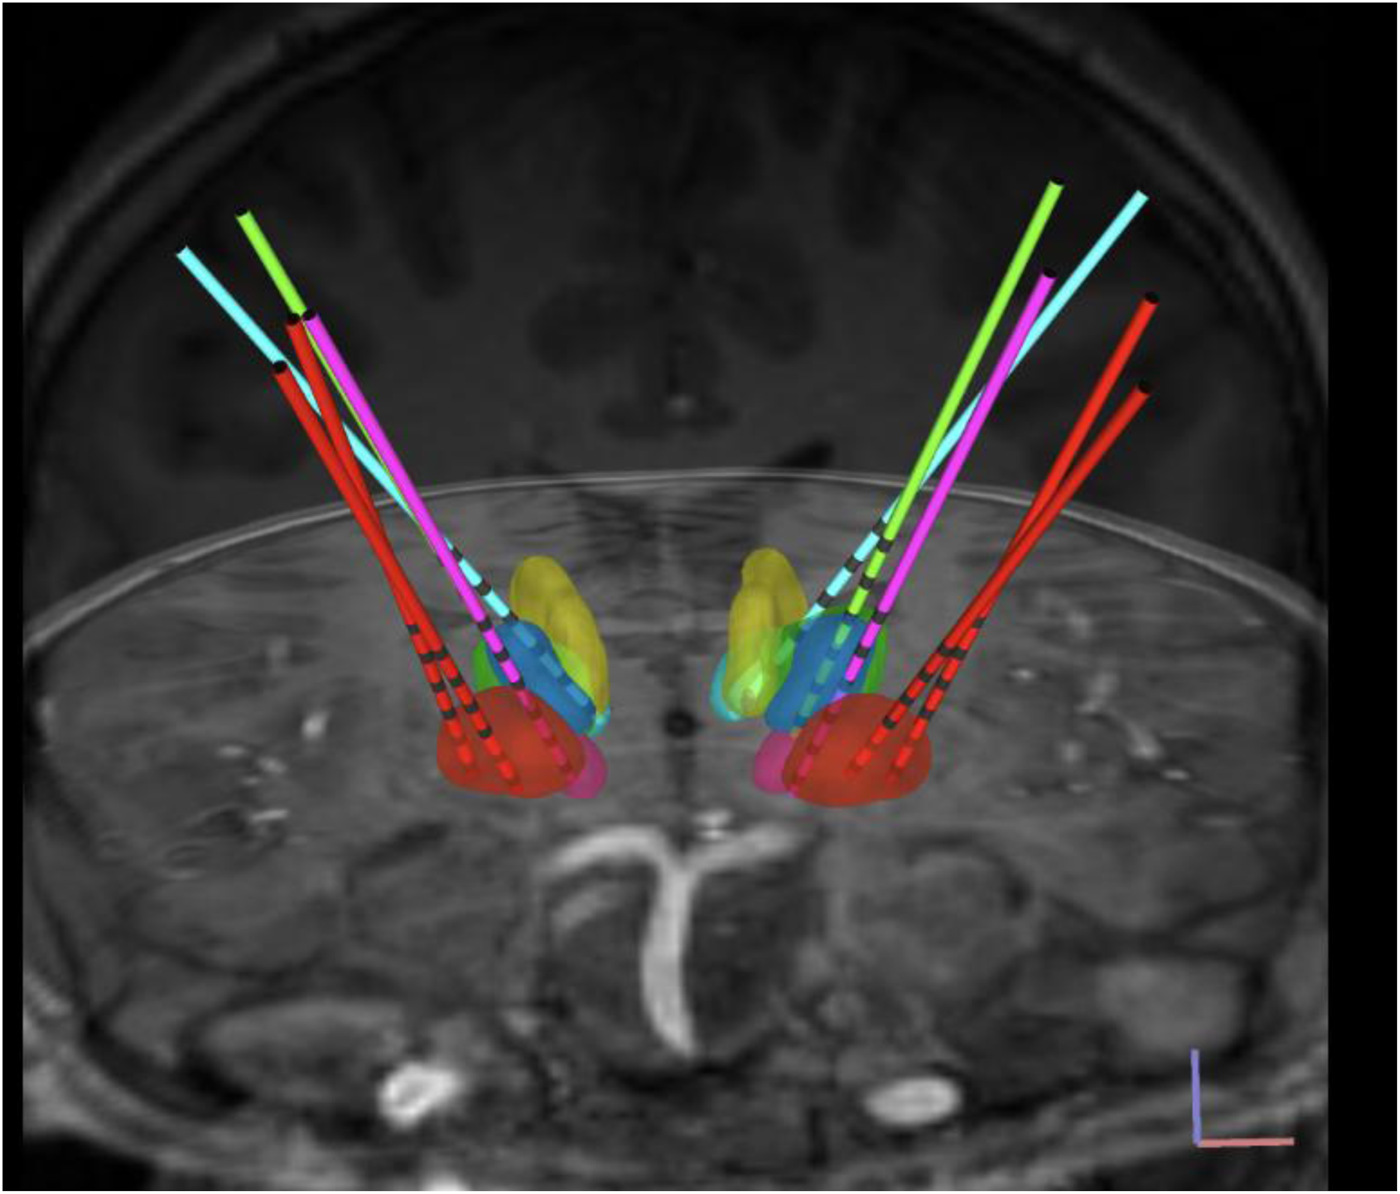

A total of 10 temporary sEEG depth leads (AdTech MM16C; AdTech Medical Instrument Corp., Oak Creek, WI, United States), approved by the FDA for clinical use, were implanted bilaterally into potential DBS targets consisting of globus pallidus internus (GPi), subthalamic nucleus (STN), ventral oralis (Vo), centromedian nucleus (CM), CL, and VIM using standard stereotactic procedure [24, 25]. Figure 2 demonstrates targeted brain nuclei and sEEG electrodes used for implantation.

FIGURE 2

Targeted brain nuclei and sEEG electrodes. View of sEEG electrodes in bilateral brain nuclei: GPi (red), Vo (blue), STN (pink), VIM (green), CM (yellow), and CL (cyan); normalized scans visualized onto the Montreal Neurological Institute (MNI) space. Deep brain region boundaries were defined with the DISTAL atlas.